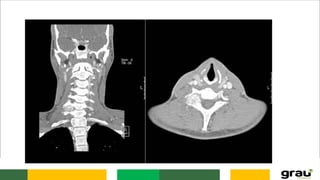

Coluna Vertebral

CURVATURAS: Primárias e secundarias

IMPORTÂNCIA CLINICA: hipercifose, hiperlordose escoliose

IMAGEM PANORÂMICA DA COLUNA !

CONDIÇÕES ANATÔMICAS DA COLUNA